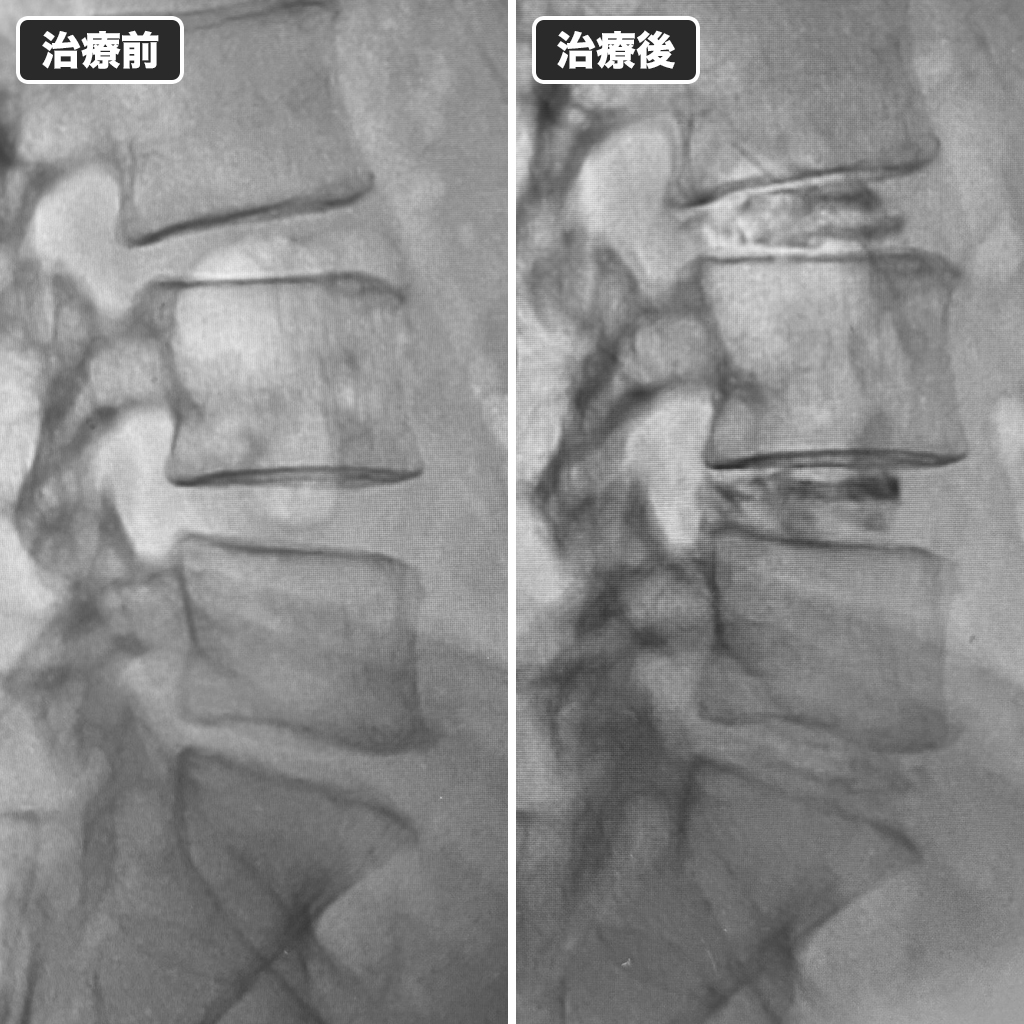

治療前後のレントゲン写真

治療前後のレントゲン写真です。左側が治療前、右側が治療後になります。春頃までに体を鍛えてゴルフを再開される予定です。